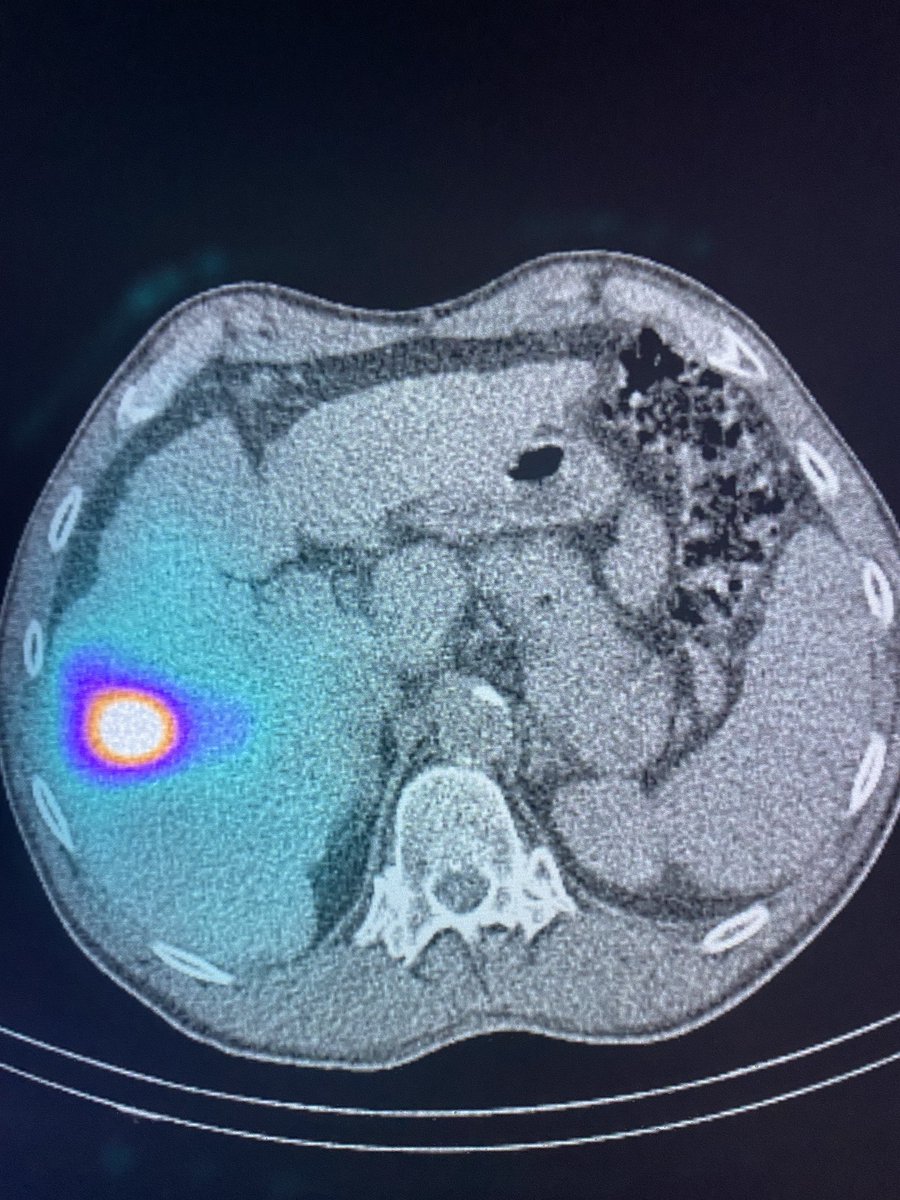

@JAMA_current Seriously? UAE if you don’t desire fertility but RF, HIFU, hyst excision, adenomyomectomy, wedge resection if you do?? Insane!!! Terrible to pub this. Womens Health July 2021! @womenirads @SIRspecialists @thefibroidlady @angiowoman @MaureenKohi @GSalazar_MD